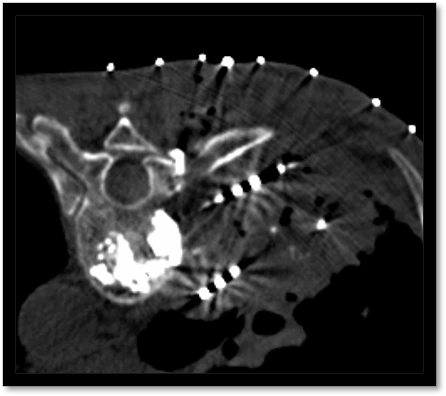

髋关节骨转移瘤

术前疼痛评分8分,髋关节活动受限,生活无法自理,术后疼痛评分3分,髋关节可自由活动